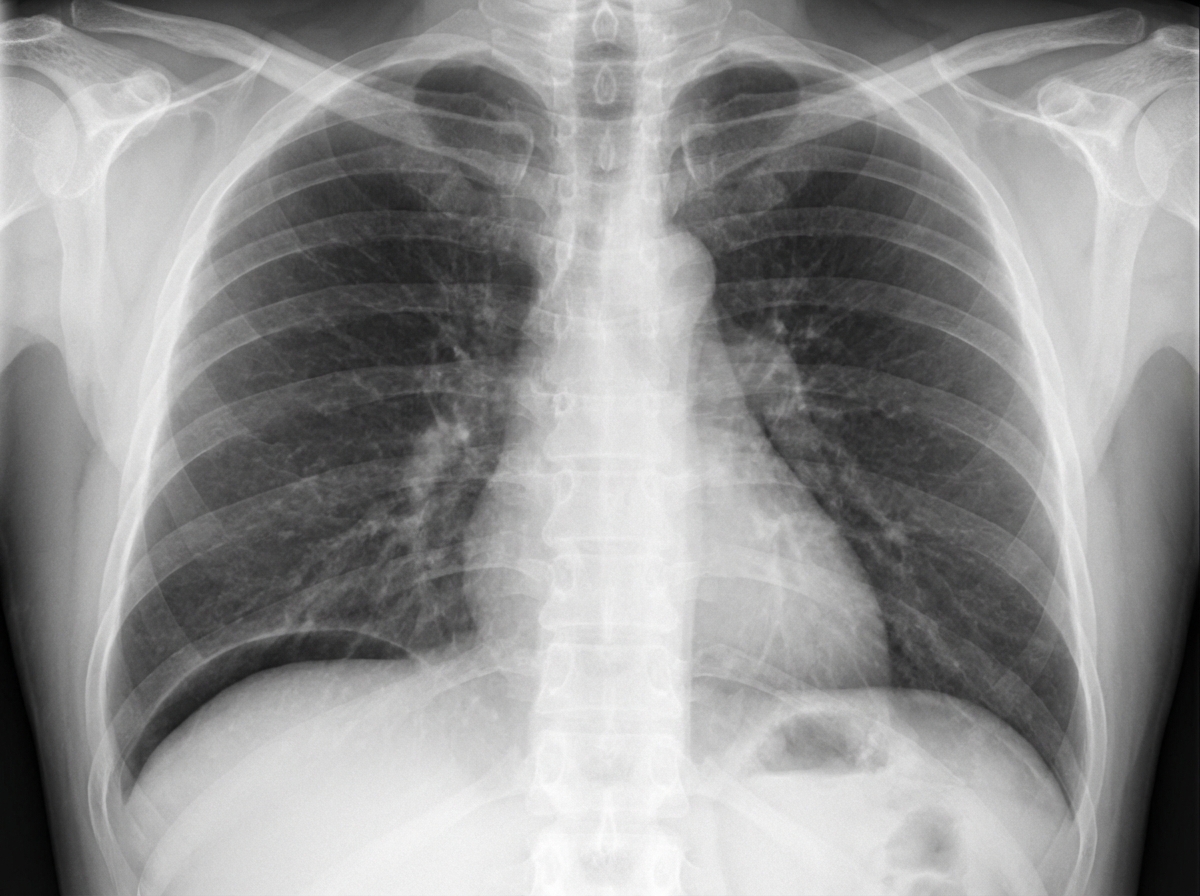

A 34-year-old male patient complains of sudden severe epigastric pain along with vomiting, tenderness, guarding. On examination there is abdominal rigidity and tachycardia. He admits to taking NSAIDs for pain. The radiological examination of the patient is given below. All statements given below are true except?

Explanation: ***Pain often radiates to groin*** - The clinical presentation (sudden severe epigastric pain, vomiting, tenderness, guarding, rigidity, tachycardia, NSAID use) and the radiological imaging showing **free air under the diaphragm** are highly suggestive of **perforated viscus**, likely a perforated peptic ulcer. - Pain from a perforated ulcer typically **radiates to the shoulder** (due to diaphragmatic irritation) or generalizes throughout the abdomen, but **not typically to the groin**. *Tenderness on per-rectal examination* - **Tenderness on per-rectal examination** can be present in cases of generalized peritonitis, as the inflammation can extend to the pelvic peritoneum. - This finding is consistent with the diffuse inflammation caused by a perforated viscus. *Blumberg sign is positive* - **Blumberg sign**, also known as **rebound tenderness**, is a classic sign of **peritoneal irritation** or peritonitis. - Given the severe abdominal pain, guarding, and rigidity, peritonitis is highly likely in this patient, making a positive Blumberg sign expected. *Dullness over flanks is observed* - **Dullness on percussion over the flanks** indicates the presence of **fluid** in the peritoneal cavity (ascites). - In a perforated viscus, gastric or intestinal contents, along with inflammatory exudates, can accumulate in the dependent areas of the abdomen, leading to dullness in the flanks.

Explanation: ***Obliteration of liver dullness*** - The image shows a **perforation** of the bowel (indicated by the arrow), which leads to the escape of **free air into the peritoneal cavity**. - **Free air under the diaphragm** displaces the liver, causing the percussion note over the liver to change from dullness to tympany, thus "obliterating" liver dullness. *Increased bowel sounds* - **Peritonitis** resulting from bowel perforation often leads to a **paralytic ileus**, characterized by **decreased or absent bowel sounds**. - Increased bowel sounds are more common in **early bowel obstruction** or gastroenteritis. *Blood on per rectal examination* - While bowel pathologies can cause rectal bleeding, a simple **perforation** without significant mucosal injury or a vascular lesion is **not typically associated with blood on per rectal examination**. - This finding is more indicative of conditions like **colitis, hemorrhoids, or rectal tumors**. *Increased air fluid levels* - **Increased air fluid levels** are typically seen on **X-rays in cases of bowel obstruction**, where fluid and gas accumulate proximal to the obstruction. - In bowel perforation, **free air is outside the bowel lumen** in the peritoneal cavity, and while some ileus might be present, increased air-fluid levels inside the bowel are not the primary or most characteristic finding. *Shifting dullness* - **Shifting dullness** is a percussion finding used to detect **free fluid (ascites)** in the peritoneal cavity, not free air. - In bowel perforation, there is **pneumoperitoneum (free air)**, which causes **tympany**, not dullness. - Shifting dullness would be found in conditions like **cirrhosis with ascites, peritoneal carcinomatosis, or tuberculous peritonitis**.